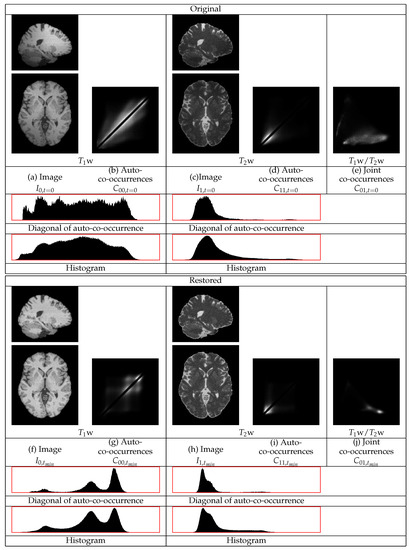

The restoration of representative w and w images with extensive non-uniformities of a Parkinson’s disease patient are shown in Figure 7. The GM tissues in the cortex, subcortical regions, and the cerebellum become of more uniform intensity both in the w and in the w images. The intensity of the WM also becomes more uniform. The statistics of the w image in Figure 7 show three different distributions corresponding to the three tissues. The diagonal auto-co-occurrences, even though they are minimally involved in the restoration, still consist of three separate distributions. The statistics of the w image also show distinct distributions for the WM and the GM even though they have a low contrast. They also show a sharper distribution corresponding to the border between the WM and the GM regions. The distribution corresponding to the CSF regions appears. This shows the successful restoration of the w image. The presence of separate tissues distributions in the statistics of the restored real images gives the entropy based measure a semantic meaning in terms of tissues intensity uniformities and tissues contrasts.

Figure 7.

Example restoration of a w and a w image pair of a Parkinson’s disease patient. The intensities of the white matter in both the w image and in the w image become more uniform. The statistical distributions become sharper.

The HCP LS images in Figure 6 and the Parkinson’s disease images in Figure 7 show that the sub-cortical regions can have a variable intensity non-uniformity effect. The restoration removes these non-uniformities. The mesencephalon and sub-cortical regions called basal ganglia and substantia nigra are implicated in Parkinson’s disease. The restoration of the uniformity in these brain regions can improve the analysis to characterize the appearance of Parkinson’s disease in MRI data [52,53].